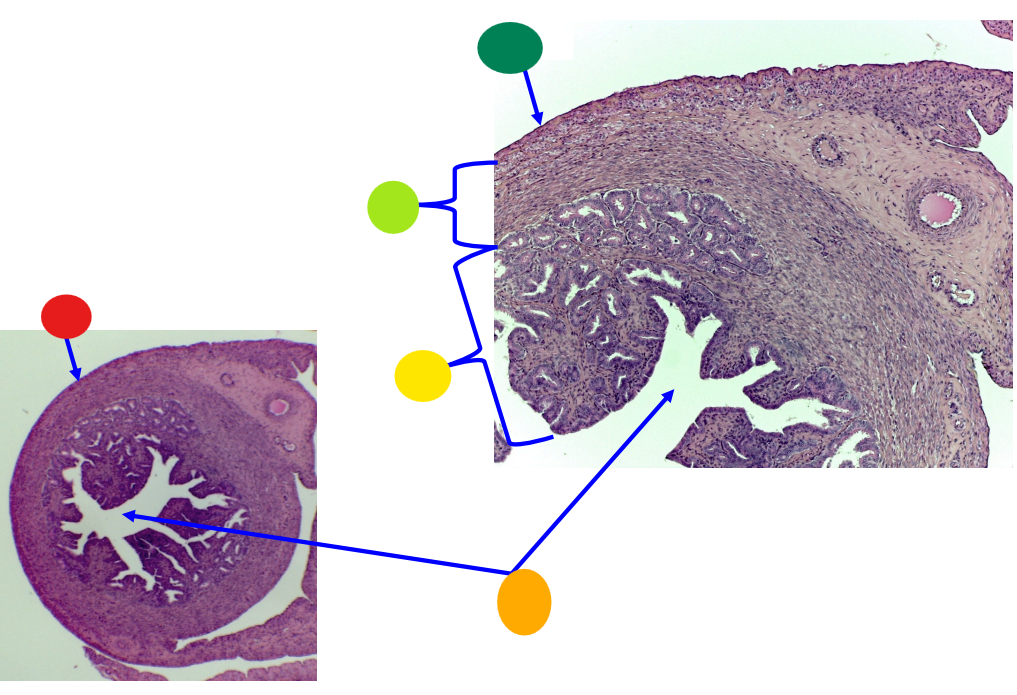

red

tunica albuginea

orange

primordial follicles

yellow

follicular cells

light green

primary oocyte

dark green

granulosa cells

light blue

primary follicles

what is this?

ovary

red

primordial follicles

red

primary follicles

red

tunica albuginea

orange

primary oocyte

yellow

primordial follicles

red

tunica albuginea

orange

primordial follicles

red

primary follicle

orange

secondary follicles

what is this

tertiary follicle